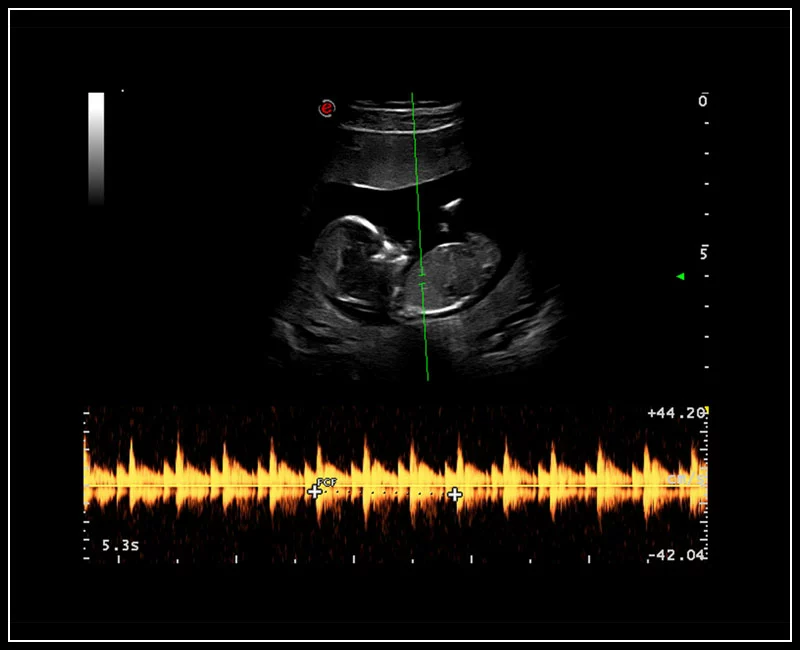

MyLab™Sigma - Umbelical cord PW Doppler mode

MyLab™Sigma - Umbelical cord PW Doppler mode